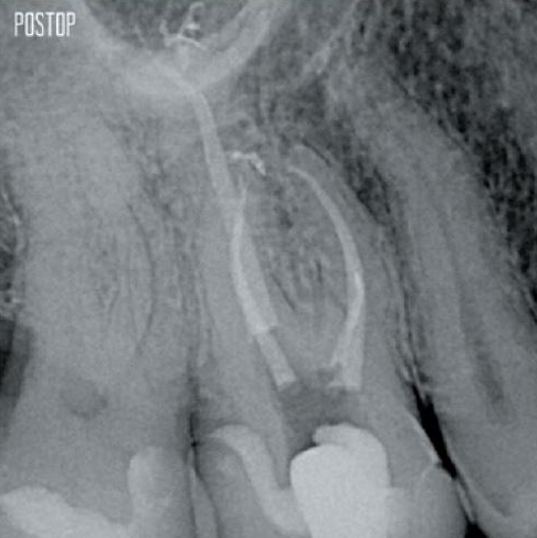

More dentin preserved. Appropiate shaping, irrigation, and obturation ensured.

Photos courtesy of Dr. Ahmed Salman